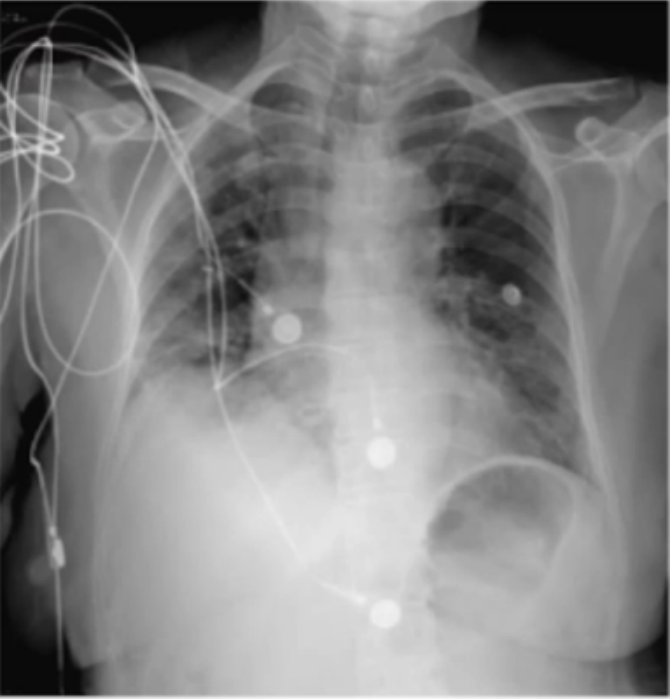

调整治疗1周后(2023-01-04)复查床旁胸片:两肺渗出较前有所吸收(图4)。复查胸部CT(2023-01-05): 两肺的磨玻璃影和渗出影较外院片显著吸收, 病变范围明显缩小(图5)

图片

4  复查床旁胸片(2023-01-04)